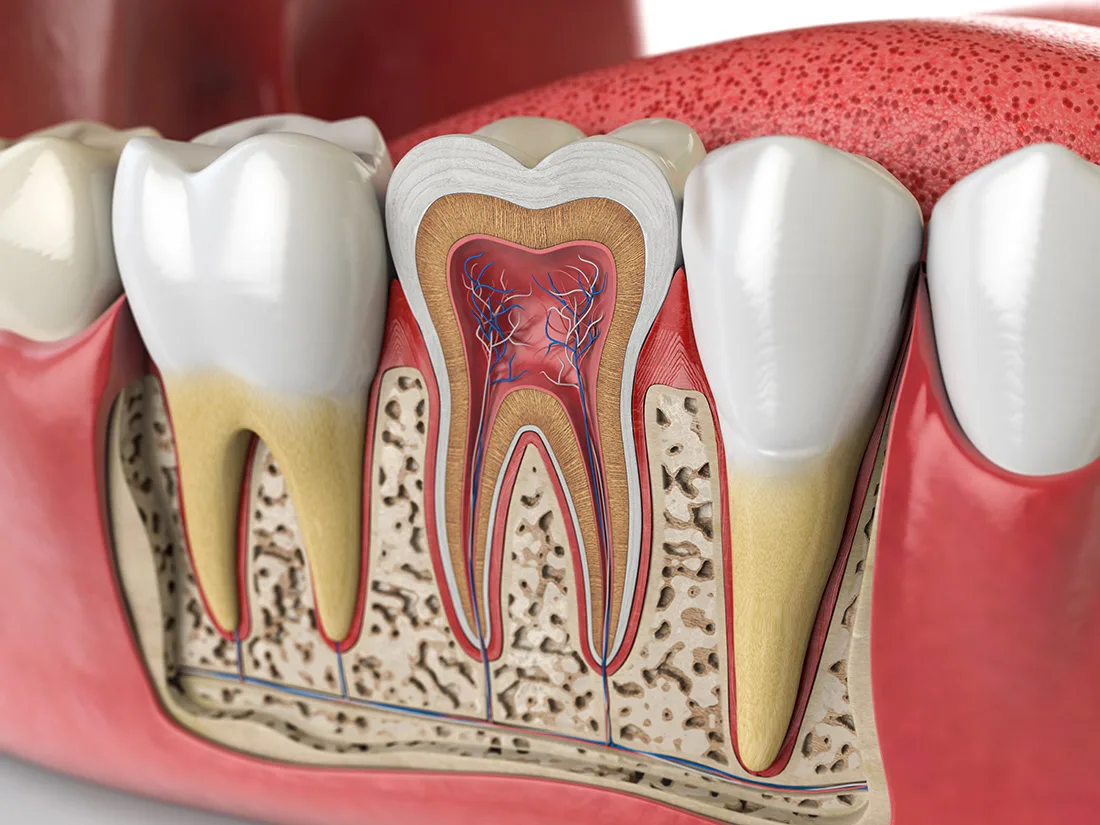

Removing Decay & Infected Pulp

Once you're fully numbed and comfortable, your dentist will begin the process of removing decayed or infected material. They'll start from the outermost layer of enamel and work their way towards the inner pulp. After removing the infected pulp, the canals will be thoroughly cleaned and flushed with a specialized disinfectant to eliminate any remaining infection.

Filling & Sealing

After cleaning and disinfecting your tooth, your dentist will fill the inner cavity with a rubbery substance called "gutta-percha". This inert material provides support to the tooth and replaces the extracted pulp. Following this, your dentist will determine whether to restore the tooth with a filling or a dental crown. This decision is based on the extent of decay and the amount of healthy enamel remaining on the tooth.